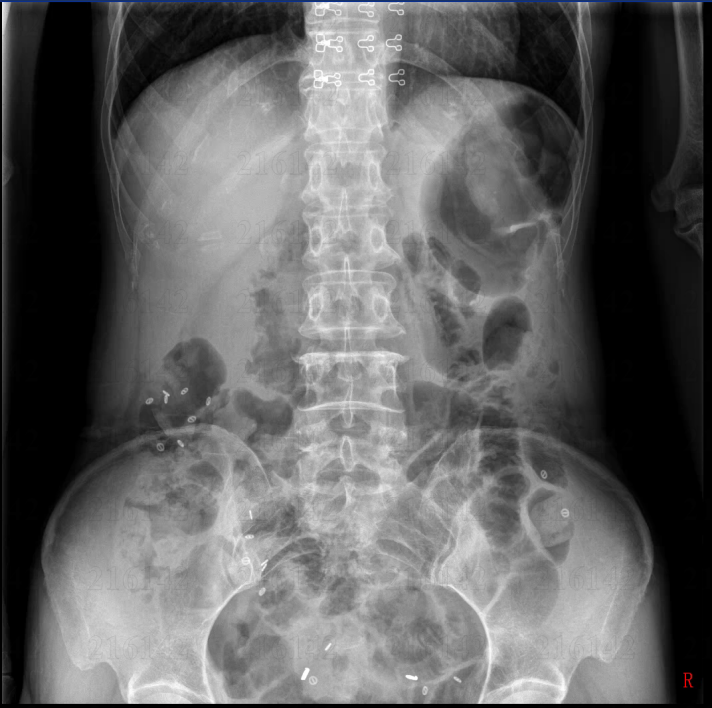

以周女士为例,72小时内即完成结肠传输试验、排粪造影等7项评估,确诊为“慢传输型便秘”合并“泻剂结肠”。MDT团队迅速给出两套方案:A方案“全结肠切除+回肠直肠吻合”;B方案“阶梯式保守治疗+肠内营养”。经充分知情并联合心理科评估,患者选择A方案。手术由王中林主任主刀,采用3D腹腔镜微创技术,出血量不足30 mL,术后第1天即可下床,第8天出院,随访1个月每日排便3~4次,营养指标全面回升。

随着饮食结构改变、精神压力增大,慢性便秘发病率已升至4%~10%,其中约一成属于“顽固性便秘”—— 经过规范的生活方式干预和足量、足疗程的泻药治疗后症状仍无明显改善,并且严重影响生活质量。面对这一“难言之隐”,温医大附二院肛肠外科牵头的MDT团队率先在省内实现“一站式”闭环管理:肛肠外科、消化内科、康复医学、临床营养、放射影像、心理健康、中医科七大学科同台会诊,3D高分辨率肛门直肠测压、盆底肌电图、结肠传输试验、排粪造影、胃肠镜检查、腹部CT等所有评估可在72小时内完成。